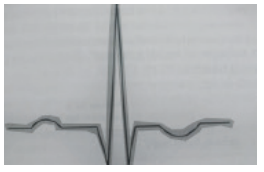

O infarto agudo do miocárdio e a angina instável caracterizam a síndrome coronariana aguda. A fgura abaixo representa uma das alterações eletrocardiográfcas encontrada nessa síndrome, denominada.

Supradesnivelamento do segmento ST

Infradesnivelamento do segmento ST

Fibrilação ventricular

Inversão da Onda T

Taquicardia ventricular